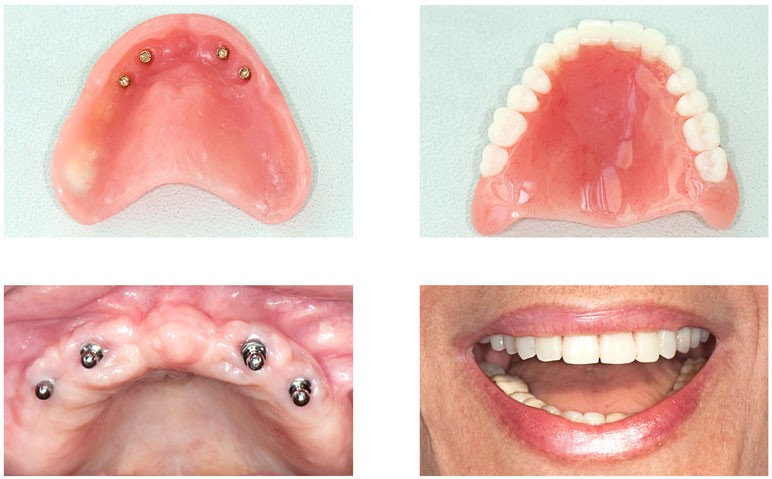

The Cost Of Dental Implants In Los Angeles

www.westlosangelesperio.com

Dental Implants Los Angeles Ca – Nlworlddesign

nlworlddesign.blogspot.com

implants